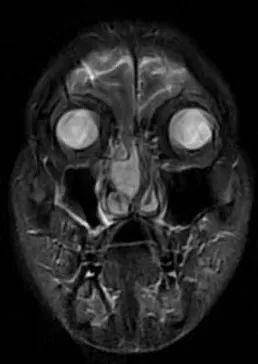

患者男,59岁,因左鼻腔涕中带血40余天入院,入院CT、MRI示前颅底肿瘤,侵犯前颅底骨质及硬脑膜。入院诊断:前颅底肿瘤。入院后在病房行活检示(左侧鼻腔)嗅神经母细胞瘤,排除手术禁忌症后行全麻下经鼻内镜下前颅底肿瘤及前颅底部分骨质磨除、硬脑膜切除,鼻颅底重建手术。

CT、MRI示前颅底肿瘤,侵犯前颅底骨质及硬脑膜